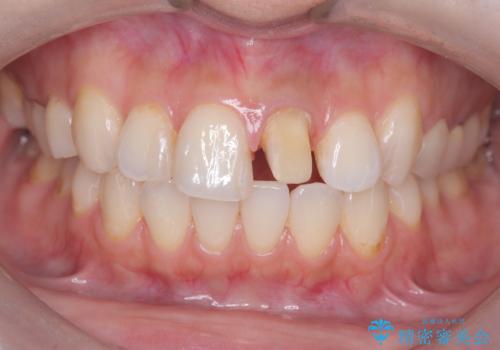

- 「前歯の色が気になる」を主訴に来院された患者様です。

前歯にプラスチックの材料が入っており、形と色が悪くなっていました。

失活歯だったため全体的に歯の色が暗くなっていました。